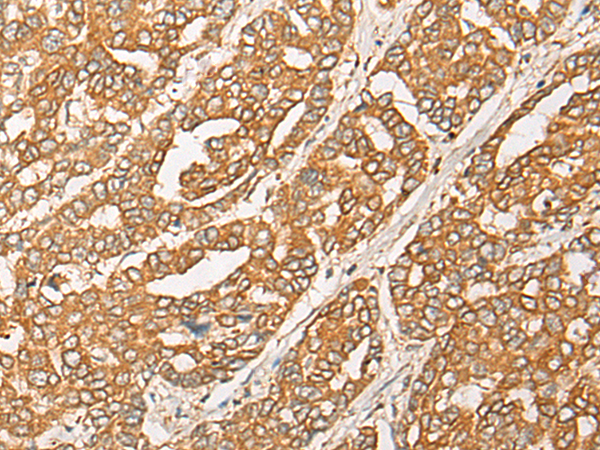

分类: 科研抗体货号: P06328别名: PAP1应用: WB,IHC反应种属: Human, Mouse